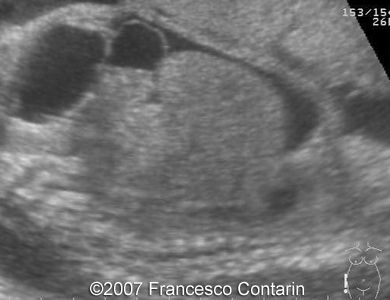

This is a 22-year-old woman (G4, P2) with unremarkable familiar history, referred to our hospital at 29 weeks of gestation due to a fetal ascites. There were no signs of maternal-fetal blood incompatibility. The ultrasound investigation revealed rhizomelia, postaxial polydactyly, small thorax, short ribs, ascites, increased abdominal biometric parameters, polyhydramnios. We supposed two diagnoses: Short rib-polydactyly syndrome versus Jeune syndrome (asphyxiating thoracic dystrophy).

Images 9, 10. 29th week of pregnancy -  fetal ascites (left); and transverse plane through narrow thorax (right).

Images 5, 6. 29th week of pregnancy -  narrow thorax.